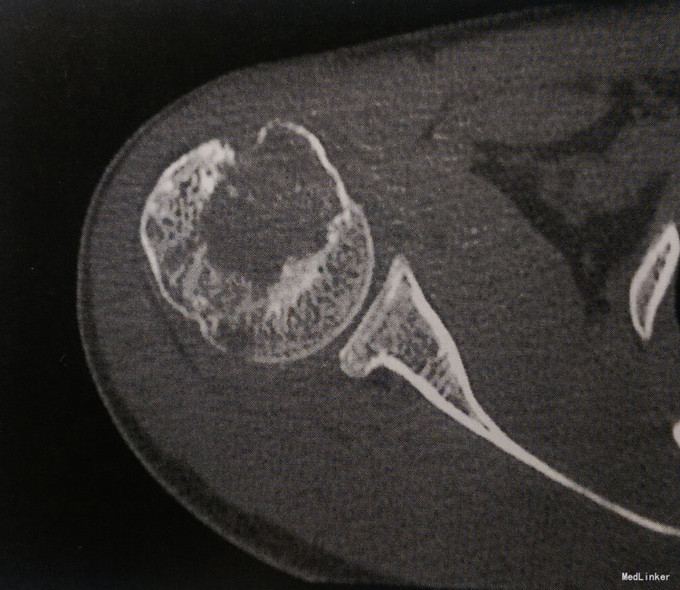

男性,21岁,右肩关节酸胀不适1月余。余无异常。

查体肩关节活动正常,无红肿。 影像学表现:CT示右侧肱骨头骨性关节面下可见囊状膨胀性骨质破坏,病灶内部密度不均匀,隐约可见点条状高密度钙化影。边缘分叶状,周边可见硬化缘,无明显骨膜增生和软组织肿胀。

诊断:右肱骨软骨母细胞瘤 治疗:手术治疗